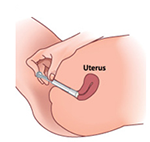

Gently insert the applicator into your vagina while you position your body in one of the two ways. Insert the applicator only as far as it will comfortably go. You can stand with your feet apart and your knees bent.

Or lie on your back with your knees bent and legs slightly apart.

Push the plunger of the applicator until it stops. Remove the applicator from the vagina.